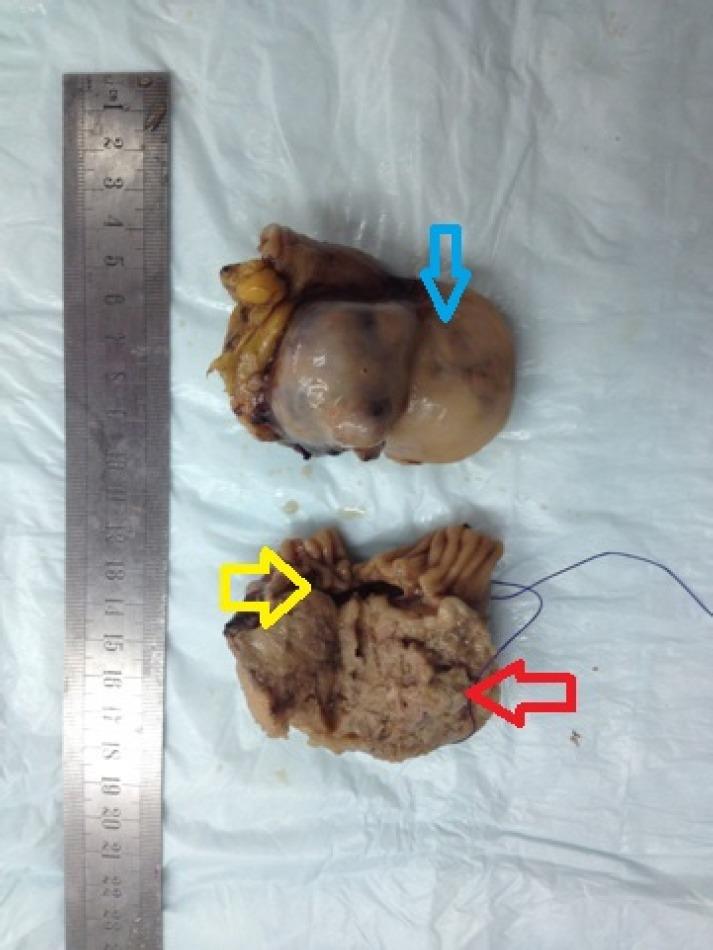

Gastrointestinal stromal tumors (GISTs) are rare tumor of the gastrointestinal tract. GISTs occur in the entire gastrointestinal tract and may also arise from the retroperitoneum, omentum and mesenteries. They are originated from gastrointestinal pacemaker cells (Cajal's interstitial cells) and range from benign tumors to sarcomas at all sites of occurrence. Diagnosis of GIST could be deceptive because of their similarity in appearance to gynecological neoplasms. We would like to present a case of a woman with GIST in the small intestine giving a imprint of an adnexal mass was diagnosed correctly during surgery. The diagnosis and treatment of GIST has been reformed over the past years. It is crucial to separate GISTs from possible misdiagnosis because their prognosis and treatment could be unlike clearly. The purpose of this case is to evaluate this rarely seen clinical entity, and thus, make some contribution to the literature.

胃肠道间质瘤(GISTs)是胃肠道的罕见肿瘤。GISTs可发生于整个胃肠道,也可能起源于腹膜后、网膜和肠系膜。它们起源于胃肠道起搏细胞(卡哈尔间质细胞),在所有发生部位的肿瘤性质从良性到肉瘤不等。由于GISTs外观与妇科肿瘤相似,其诊断可能具有欺骗性。我们在此呈现一例小肠GISTs患者的病例,该患者在手术中被正确诊断,其表现曾被误诊为附件肿物。在过去几年中,GISTs的诊断和治疗方法已经有所革新。将GISTs与可能的误诊区分开来至关重要,因为它们的预后和治疗方法可能有明显不同。本病例的目的是评估这种罕见的临床实体,从而为相关文献做出一些贡献。